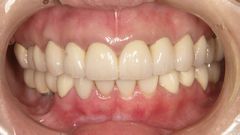

今日はその中でも、「仮歯での噛み合わせのバランスを整える治療」について例を出して説明していきます。

20代の女性ですが、ほとんどの歯が虫歯で奥歯は抜けてしまったところもあります。

当然ですが奥では食事ができないとのことでした。

まずは虫歯の治療や根の治療、そして歯茎の治療をしていきます。

これは土台工事のようなもので、ここがしっかりとしていないと後で大変なことになります。

仮歯にて噛むこと、会話すること、飲み込むことが問題なくできて、噛み合わせが安定したのを確認した上で完成となりました。

ただ綺麗な歯を入れるだけではしかっりと噛めるとは限りませんし、長持ちするのは難しいでしょう。

口の中が壊れている場合は仮歯でのリハビリは必須と言えます。